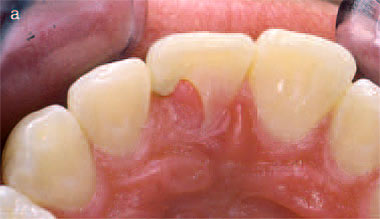

Fig. 3. (a) Labial surface of the dentition of a 19-year-old male.Aslight

reddish irregularity can be seen at the gingival margin of themaxillary

right lateral incisor. (b)Radiograph of the maxillary right lateral incisor.

A small radiolucency

corresponds to the overlying lesion. From (1). Reproduced with permission

from Quintessence Publishing. |

Class 1

Some early lesions which are in this category may show a slight irregularity

in the gingival contour associated with a surface defect containing soft tissue

which bleeds on probing (Fig. 3a). A radiograph will usually show a small coronal

radiolucency corresponding to the lesion (Fig. 3b).